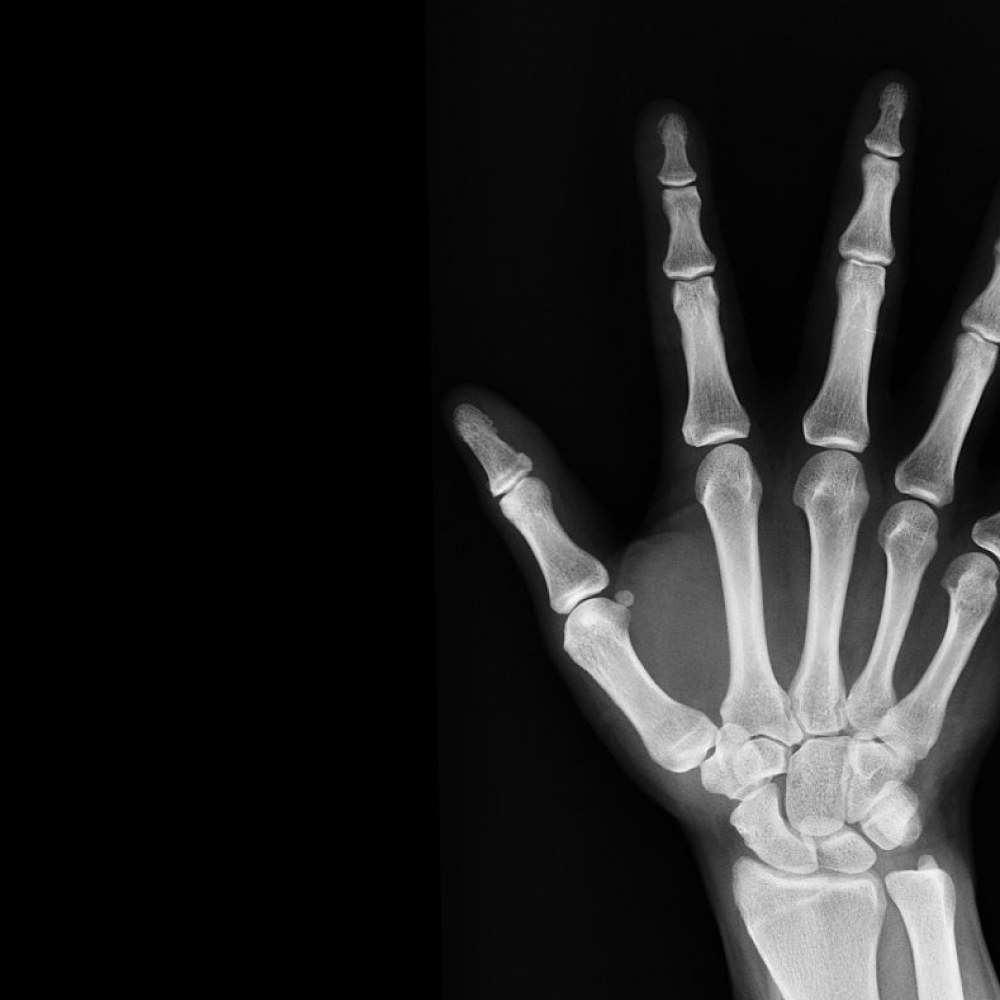

X-Ray

Best X-Ray Centre in Malleshwaram

Medical x-rays are used to generate images of tissues and structures inside the body. If x-rays travelling through the body also pass through an x-ray detector on the other side of the patient, an image will be formed that represents the “shadows” formed by the objects inside the body.Visit our center as we have some best facilities we are the >best X ray centre in malleswaram.